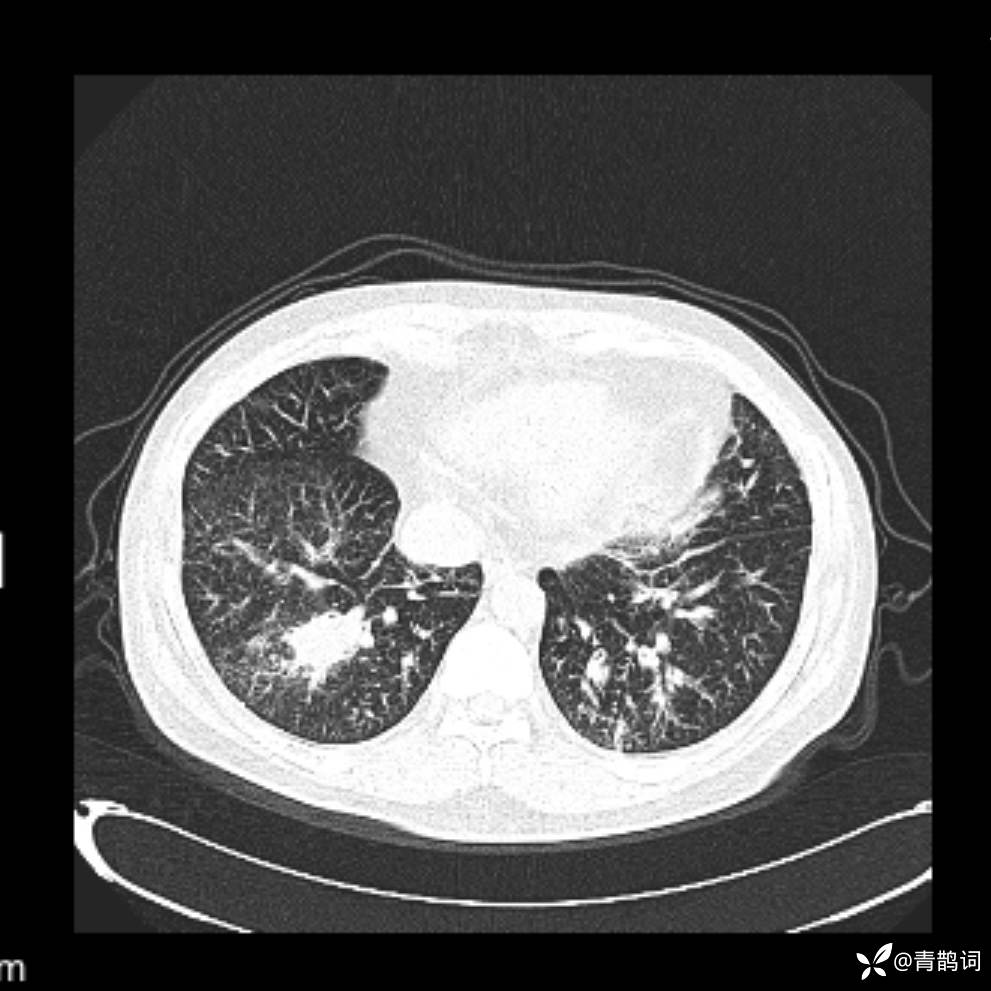

患者年龄:30岁。

患者性别:男。

简要病史:左颜面部肿胀2年,反复咳嗽咳痰,逐渐加重。

辅助检查

结合病史及影像学表现,期待评论区各位老师各抒己见~